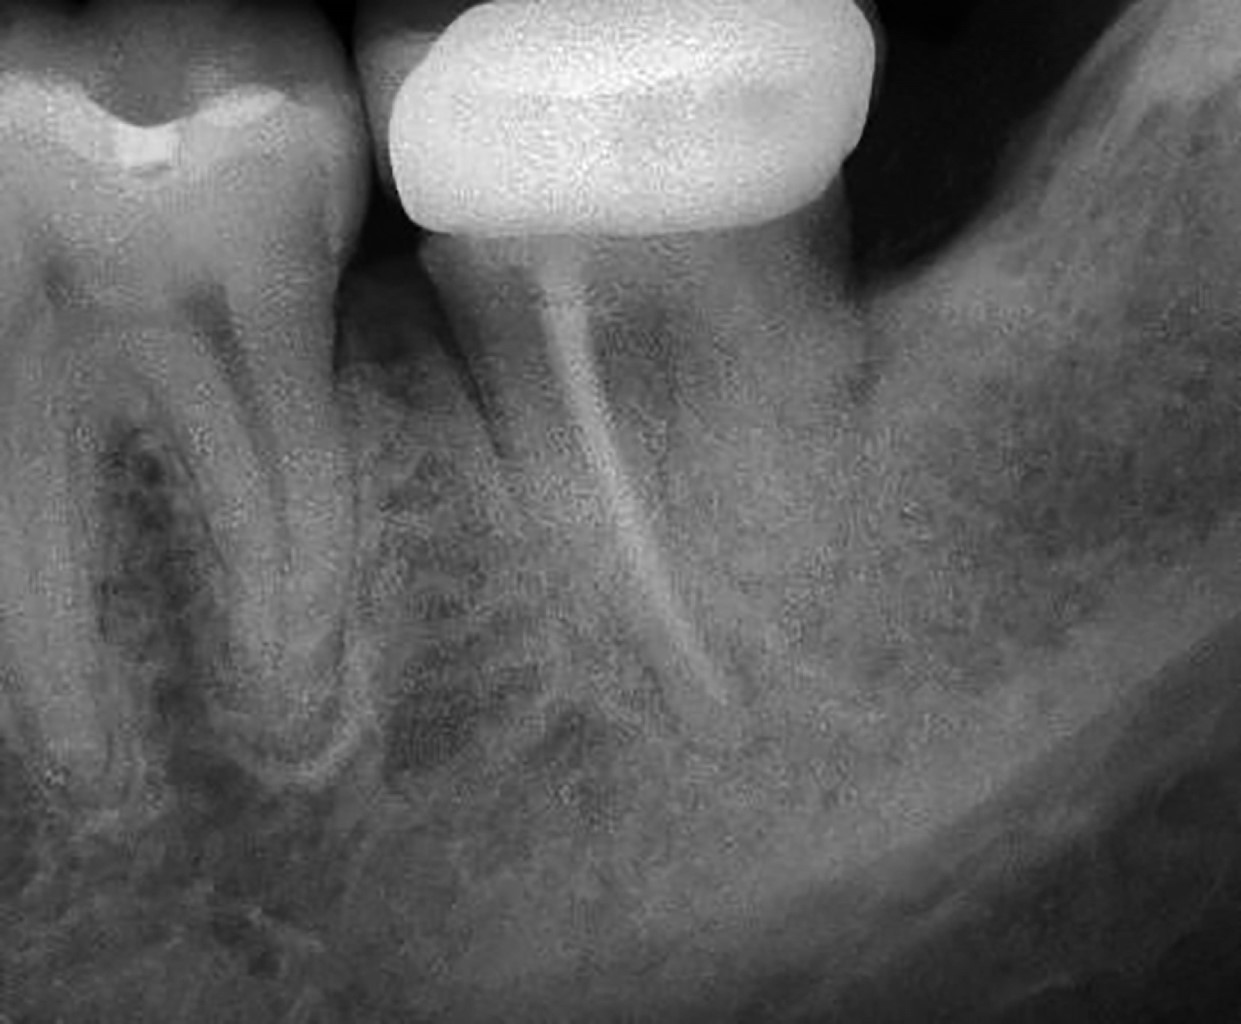

La radiografía muestra una superposición de imágenes entre la corona del tercer molar retenido y la raíz distal del segundo molar, que no permite observar la raíz distal del segundo molar.

La corona del segundo molar presenta zonas radiopacas en la corona en sus caras mesial y oclusal, presenta además una cámara pulpar amplia, es visible una línea radiolúcida en la raíz mesial, compatible con uno de los canales radiculares mesiales de tamaño delgado y con ligeras curvaturas hacia distal y mesial, también se observa una línea radiolúcida en la superficie mesial de la misma raíz, compatible con ensanchamiento ligero del espacio del ligamento periodontal, que se extiende hasta la zona periapical.

Se decide extraer el tercer molar, procedimiento que fue realizado por un cirujano maxilofacial, sin complicaciones aparentes. Después de tres semanas el paciente acude nuevamente refiriendo dolor en la zona del segundo molar izquierdo, se toma una nueva radiografía donde se observa pérdida de continuidad de la imagen del tercio medio y apical de la raíz distal (Figura 2).

Figura 2